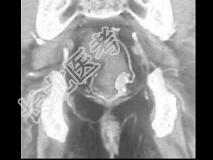

- 单项选择题男,50岁, 血便,大便形状改变, CT如图所示,最可能的诊断是 ( )

A、直肠息肉

B、直肠内粪便

C、直肠癌

D、直肠腺瘤

E、直肠淋巴瘤